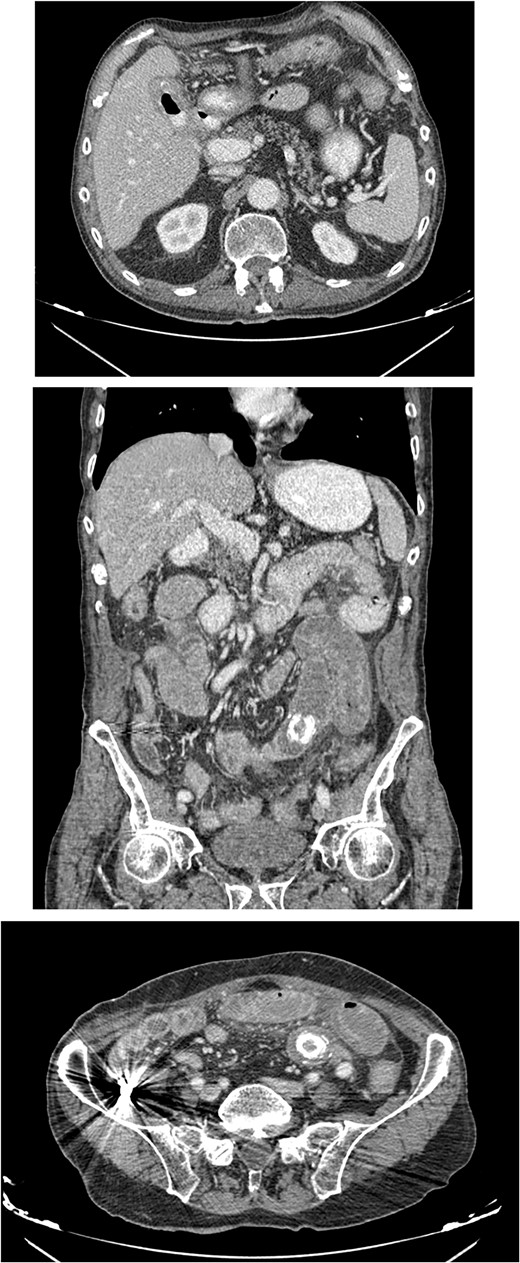

The patient was then admitted to the General Surgery department and treatment with broad-spectrum antibiotics (piperacillin/tazobactam and metronidazole) was initiated. On the second day of hospitalization, the patient underwent a repeat CT scan which indicated presence of air and oral contrast in the gallbladder, pneumobilia, swelling of the pylorus, and small bowel obstruction with the transition point being further into the ileum compared with the first CT scan (Fig. 1). Based on the comparison of the CT scan findings and past medical history of acute cholecystitis, gallstone ileus was established as the most possible diagnosis and the patient was led to the operating room.

CT images of the abdomen revealed small bowel obstruction due to gallstone and presence of air and oral contrast into the gallbladder.